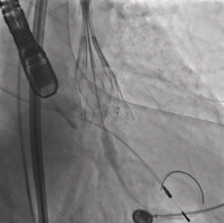

全降解封堵器成功治疗紧邻主动脉瓣嵴下型室缺